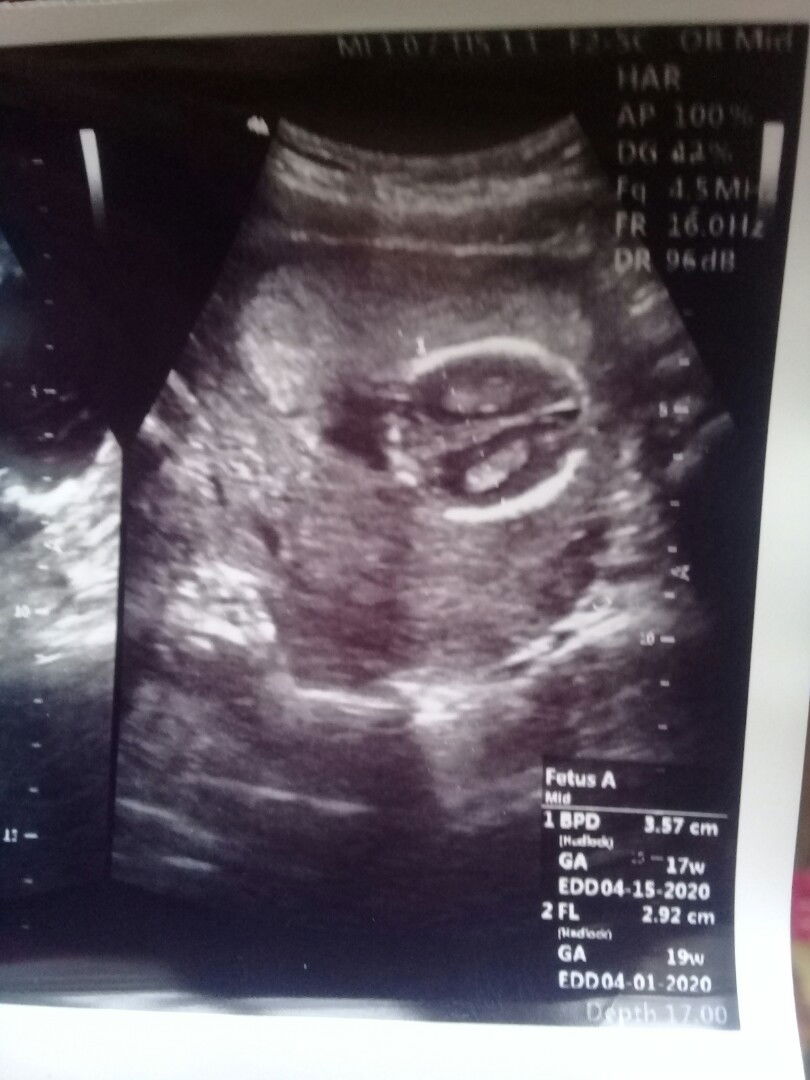

Tulisan2 di bawah itu maksd.a apa ya bun di singkat2 gak ngerty aku.